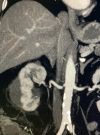

Herein, we report a patient who underwent percutaneous cryoablation for suspected renal cell carcinoma and developed a subcapsular hematoma with numerous pseudoaneurysms and dramatic structural deformity. Despite the severity suggested by the radiologic presentation, a conservative management approach was selected due to the patient's favorable hemodynamic status. This resulted in a positive outcome as alternative treatment options would have resulted in loss of the organ.